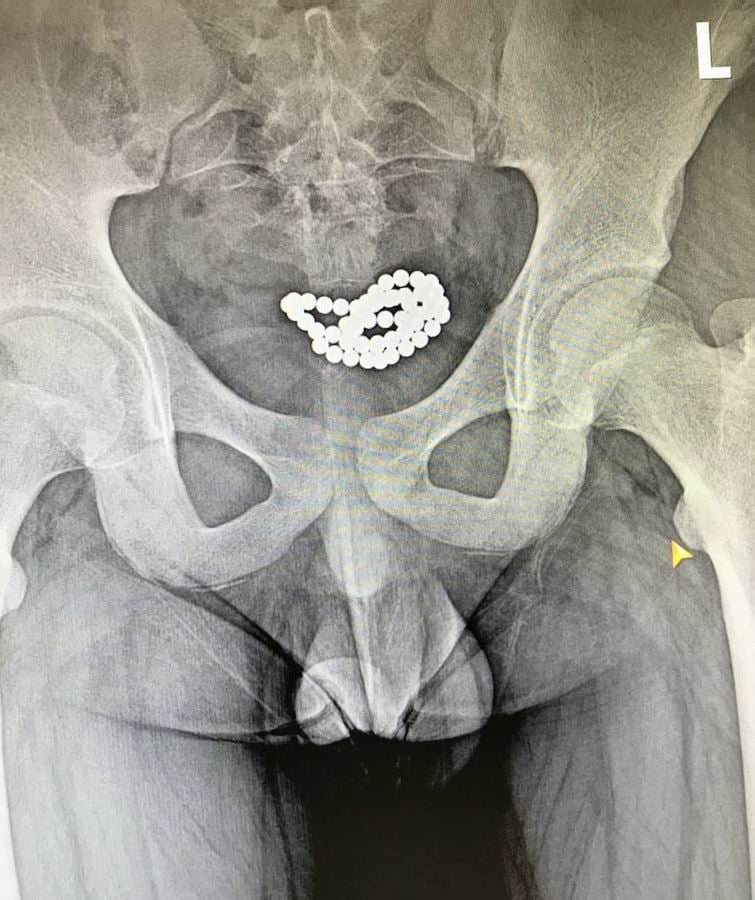

За останні три місяці в нашому закладі успішно було прооперовано два ідентичні випадки евакуації магнітних кульок з сечового міхура хлопчиків віком 10-15 років. В обох випадках було виконано цистотомію міні-лапаротомним доступом з подальшим вилученням 62 та 24 магнітних кульок.

Післяопераційний період у цих пацієнтів пройшов без ускладнень, і вони були виписані додому у задовільному стані», – йдеться у дописі.